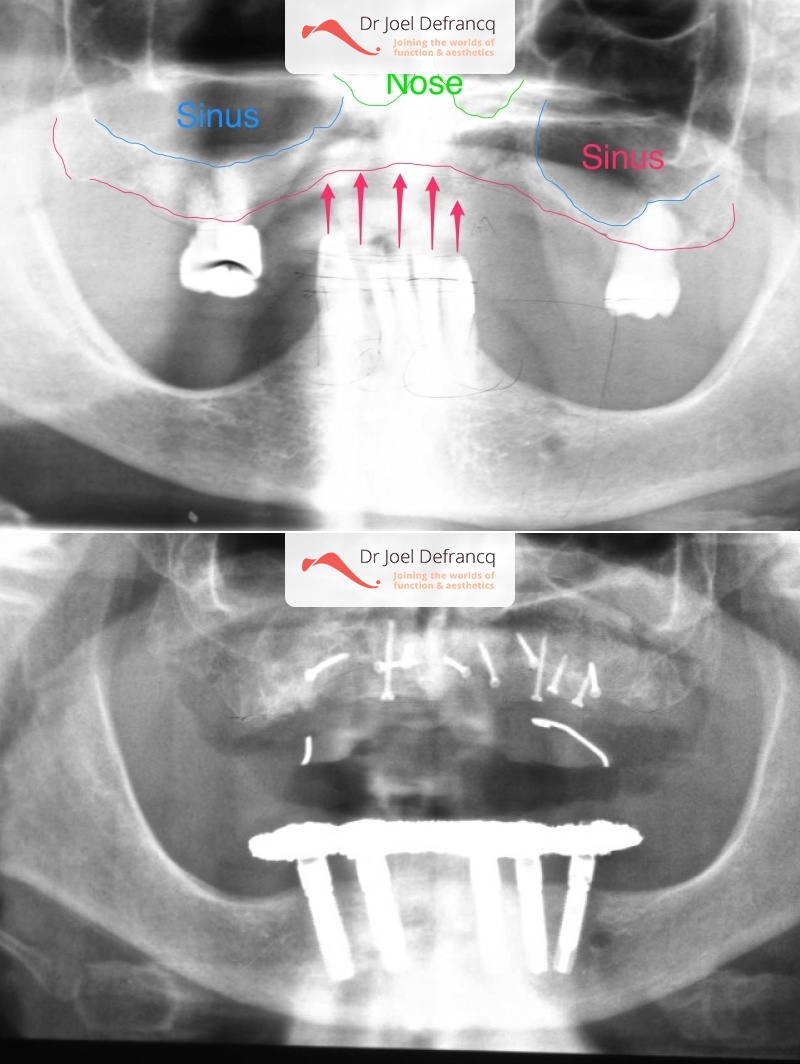

Dentale diagnose

- Klasse I

Behandeling tandheelkundige implantaten

- Vaste tanden op implantaten (bovenkaak)

- Vaste tanden op implantaten (onderkaak)

- Implantaten met beenopbouw